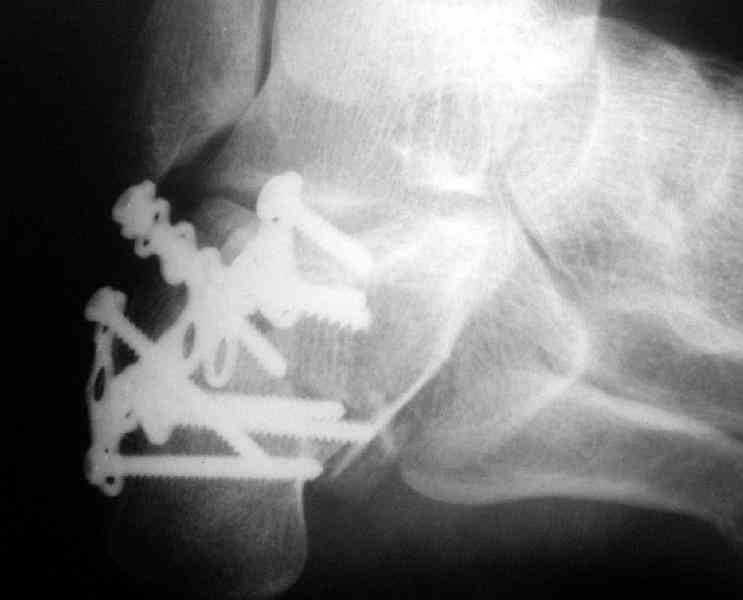

Re: Перелом пяточной кости

Пяточной пластиной

Какой предпочитаете доступ? Нет ли показательных рентгенснимков?